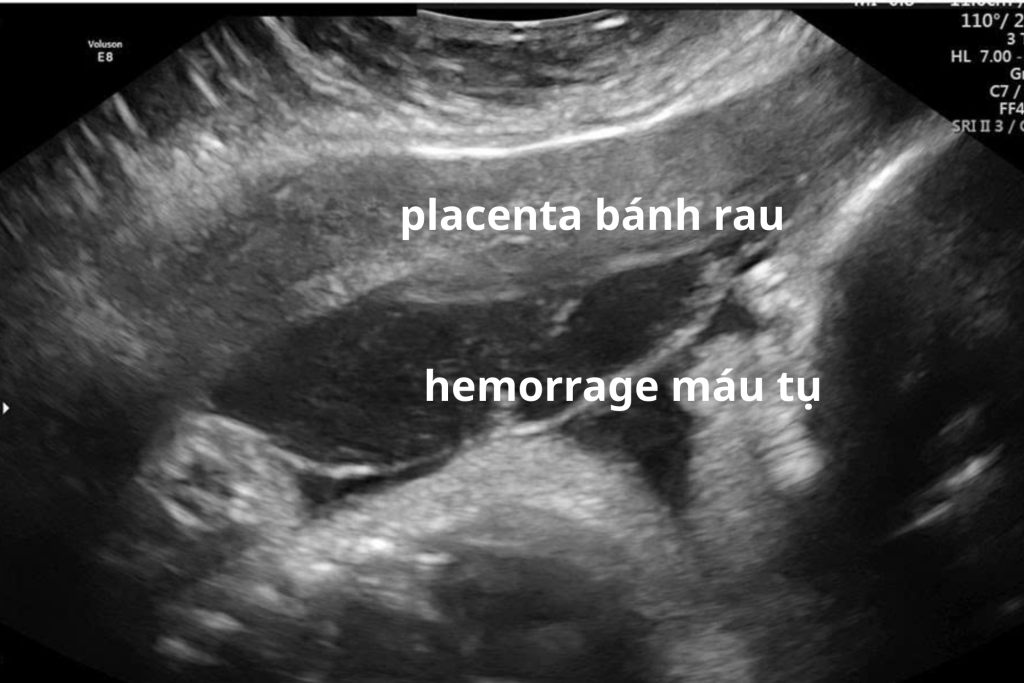

- Máu có thể tụ phía sau bánh nhau

Nghi ngờ nhau bong non trên siêu âm có chắc chắn không?

Siêu âm có thể hỗ trợ phát hiện khối máu tụ sau bánh nhau. Tuy nhiên:

- Không phải mọi trường hợp đều nhìn thấy rõ trên siêu âm

- Giai đoạn sớm có thể chưa có hình ảnh đặc hiệu

- Siêu âm bình thường không loại trừ hoàn toàn nhau bong non

Vì vậy, khi tìm hiểu dấu hiệu nhau bong non là gì, cần hiểu rằng triệu chứng lâm sàng quan trọng hơn hình ảnh siêu âm trong nhiều trường hợp.